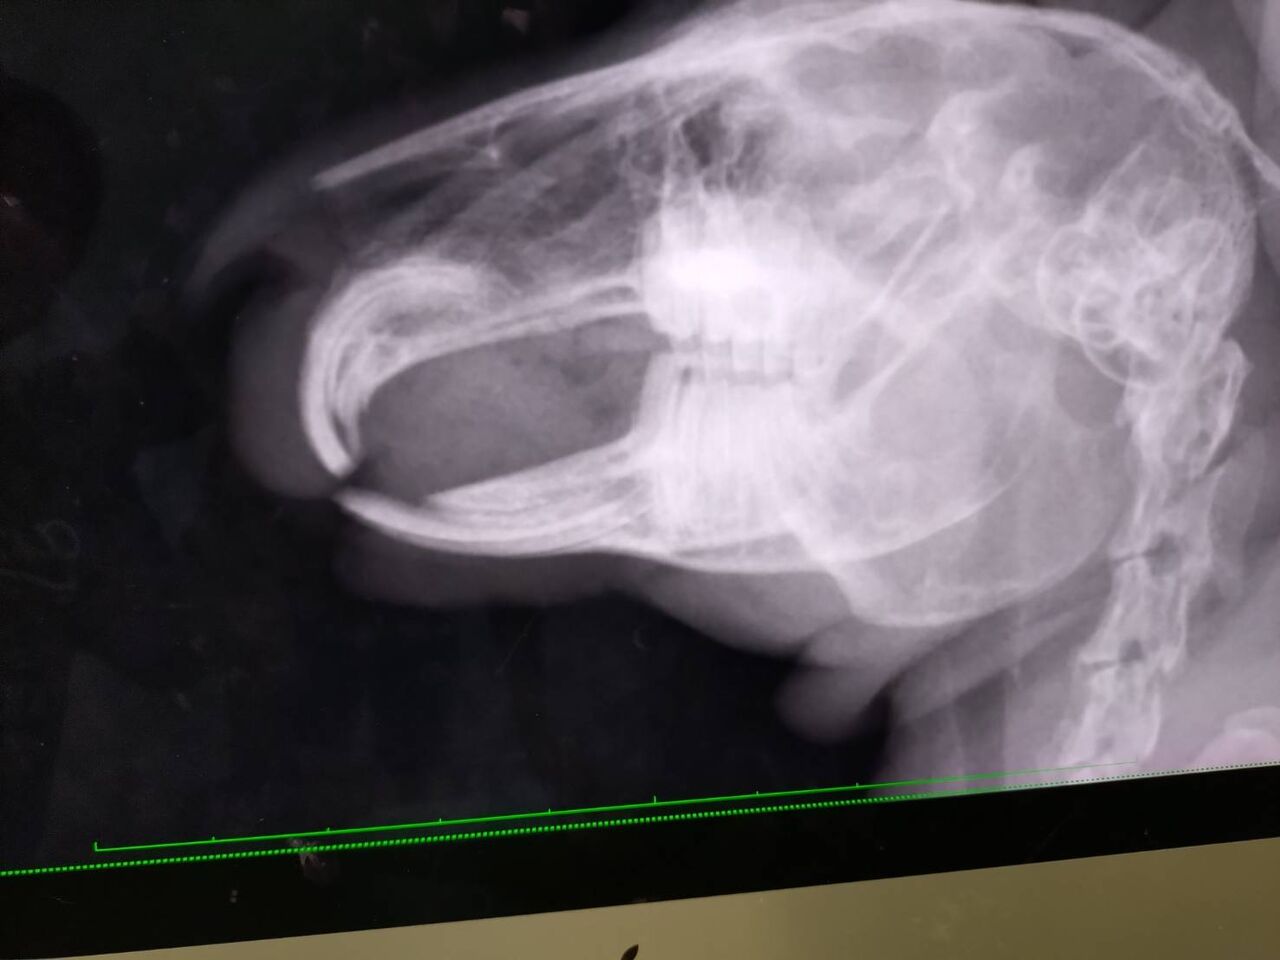

ベルくん【師走っこ】

3月に食欲が落ち、歯が伸びていたのが原因だったため定期的に通院しています

6/28 食欲不振で通院

ヨダレっぽい症状あり、口腔内チェックと念のためレントゲンも撮りました

内側に伸びた右下の歯をカット

血もにじんでいたので、これがヨダレの原因かも…とのこと

胃もガスが多めで、預かりさんが注意深く見守って下さっています